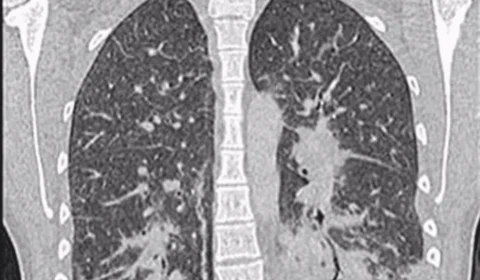

‘Pulmão de pipoca’: conheça a doença bizarra que o vape causou nesta adolescente

Adolescente de 17 anos desenvolve doença pulmonar irreversível após três anos usando cigarro eletrônico para controlar ansiedade durante a pandemia.